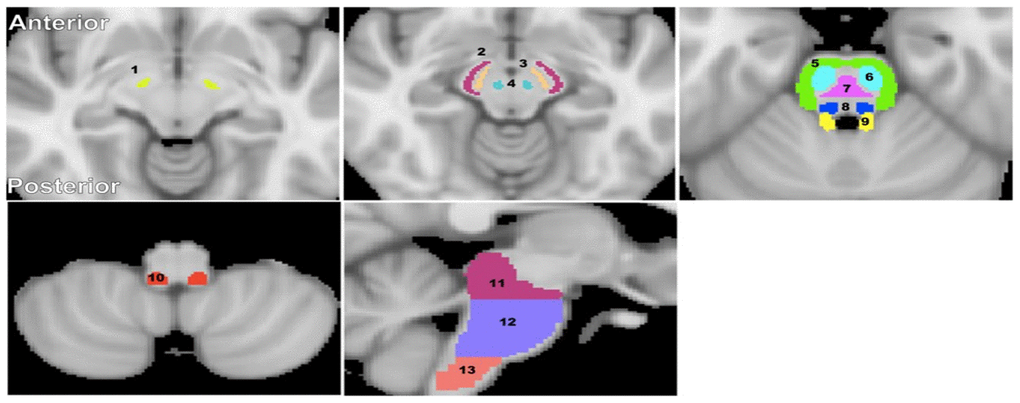

Figure 5. Visualization of the brainstem WM and GM ROIs studied. (1) Subthalamic nucleus, (2) Cerebral peduncle, (3) Substantia nigra, (4) Red nucleus, (5) Middle cerebellar peduncle, (6) Corticospinal tract, (7) Pontine tract, (8) Lemniscus tract, (9) Superior cerebellar peduncle, (10) Inferior cerebellar peduncle, (11) Midbrain, (12) Pons, and (13) Medulla. The brainstem structural images were obtained from the standard MNI atlas. Representative slices were chosen for visualization.

Fourteen brainstem structures were chosen as regions of interest (ROIs) from the Johns Hopkins University (JHU) ICGM-DTI 81 atlas [66, 67] and the Talairach structural atlas provided in FSL to cover all the ROIs for this investigation (Figure 5). ROIs were manually adjusted on single subject-level when needed to reduce partial volume effects and imperfect image registration. Six independent, non-overlapping, white matter ROIs were derived from the JHU atlas; these were the superior cerebellar peduncle, middle cerebellar peduncle, inferior cerebellar peduncle, corticospinal tract, lemniscus tract, and pontine tract. Four additional white matter ROIs were derived from the Talairach atlas corresponding to the midbrain, pons, medulla, and whole brainstem white matter, while three independent, non-overlapping, gray matter ROIs were derived from the same atlas corresponding to the substantia nigra, red nucleus, and subthalamic nucleus. Of note, the pons, medulla, midbrain, and whole brainstem WM ROIs obtained from the Talairach structural atlas encompass all WM within the 10 anatomical subdivisions. The GM within these ROIs was excluded.